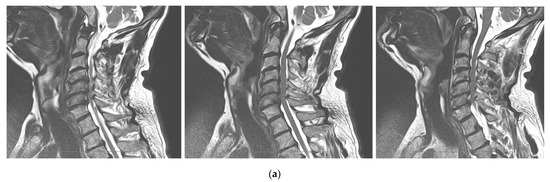

Chiari 1 Malformation (CM1) is classically defined as a caudal displacement of the cerebellar tonsils through the foramen magnum into the spinal cord. Modern imaging techniques and experimental studies disclose a different etiology for the development of CM1, but the main etiology factor [...] Read more.

Chiari 1 Malformation (CM1) is classically defined as a caudal displacement of the cerebellar tonsils through the foramen magnum into the spinal cord. Modern imaging techniques and experimental studies disclose a different etiology for the development of CM1, but the main etiology factor is a structural defect in the skull as a deformity or partial reduction, which push down the lower part of the brain and cause the cerebellum to compress into the spinal canal. CM1 is classified as a rare disease. CM1 can present with a wide variety of symptoms, also non-specific, with consequent controversies on diagnosis and surgical decision-making, particularly in asymptomatic or minimally symptomatic. Other disorders, such as syringomyelia (Syr), hydrocephalus, and craniocervical instability can be associated at the time of the diagnosis or appear secondarily. Therefore, CM1-related Syr is defined as a single or multiple fluid-filled cavities within the spinal cord and/or the bulb. A rare CM1-related disorder is syndrome of lateral amyotrophic sclerosis (ALS mimic syndrome). We present a unique clinical case of ALS mimic syndrome in a young man with CM1 and a huge singular syringomyelic cyst with a length from segment C2 to Th12. At the same time, the clinical picture showed upper hypotonic-atrophic paraparesis in the absence of motor disorders in the lower extremities. Interestingly, this patient did not have a disorder of superficial and deep types of sensitivity. This made it difficult to diagnose CM1. For a long time, the patient’s symptoms were regarded as a manifestation of ALS, as an independent neurological disease, and not as a related disorder of CM1. Surgical treatment for CM1 was not effective, but it allowed to stabilize the course of CM1-related ALS mimic syndrome over the next two years. Full article